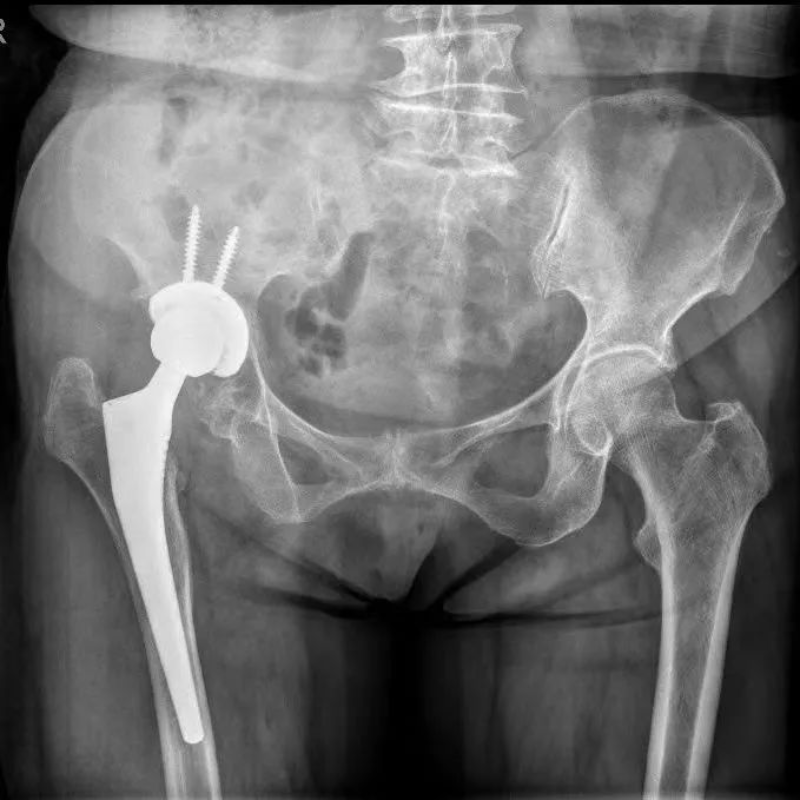

△術(shù)后

50多歲的朱大哥,20多年前因為車禍傷導(dǎo)致股骨頭缺血性壞死,一直一瘸一拐走路,就診時,右側(cè)髖關(guān)節(jié)股骨頭基本消失,髖臼磨損嚴(yán)重,關(guān)節(jié)已接近融合,肢體短縮有6-7cm,通過術(shù)前AI規(guī)劃,能精準(zhǔn)確定截骨的位置,髖臼杯安放的角度和尺寸等。手術(shù)進(jìn)展順利,術(shù)后關(guān)節(jié)功能恢復(fù)良好,肢體短縮明顯糾正無神經(jīng)損傷等并發(fā)癥,一個月后復(fù)查關(guān)節(jié)穩(wěn)定,患者從此告別一瘸一拐的日子。